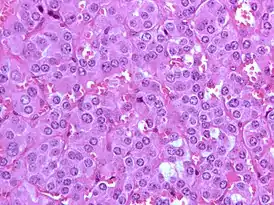

Микропрепарат феохромоцитомы.